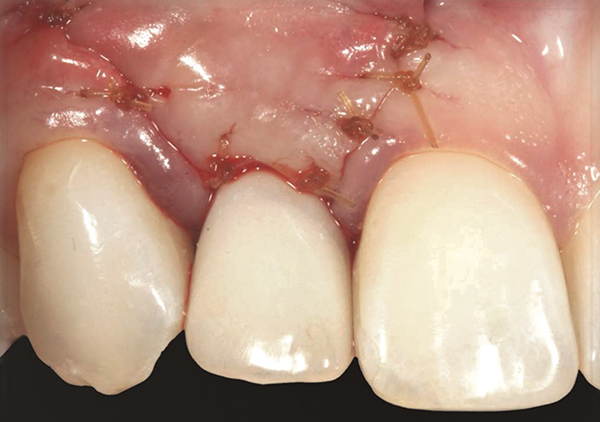

Fig 17. Vertical and horizontal incisions were sutured to attain primary closure.

Figure 17